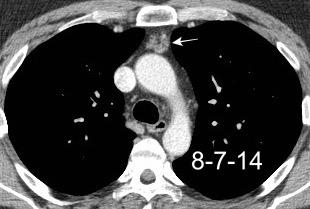

Hodgkin clásico de esclerosis nodular.

Adenopatías región cervical y mamaria interna, prevasculares y VAP. Doble contorno aórtico.